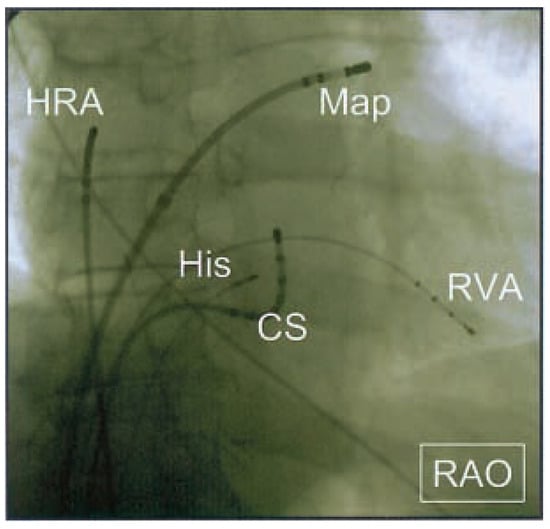

Abbildung 3. Fluoroskopisches Bild während Ablation (RAOProjektion). Der MappingKatheter (Map) liegt tief im linken Vorhofohr. CS = Katheter im Sinus coronarius; HRA = Katheter im hohen rechten Vorhof; His = Katheter in His-Position.